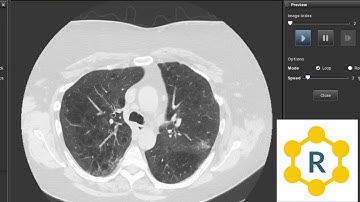

Computed Tomography (CT) Physics - Slice Thickness and Interval